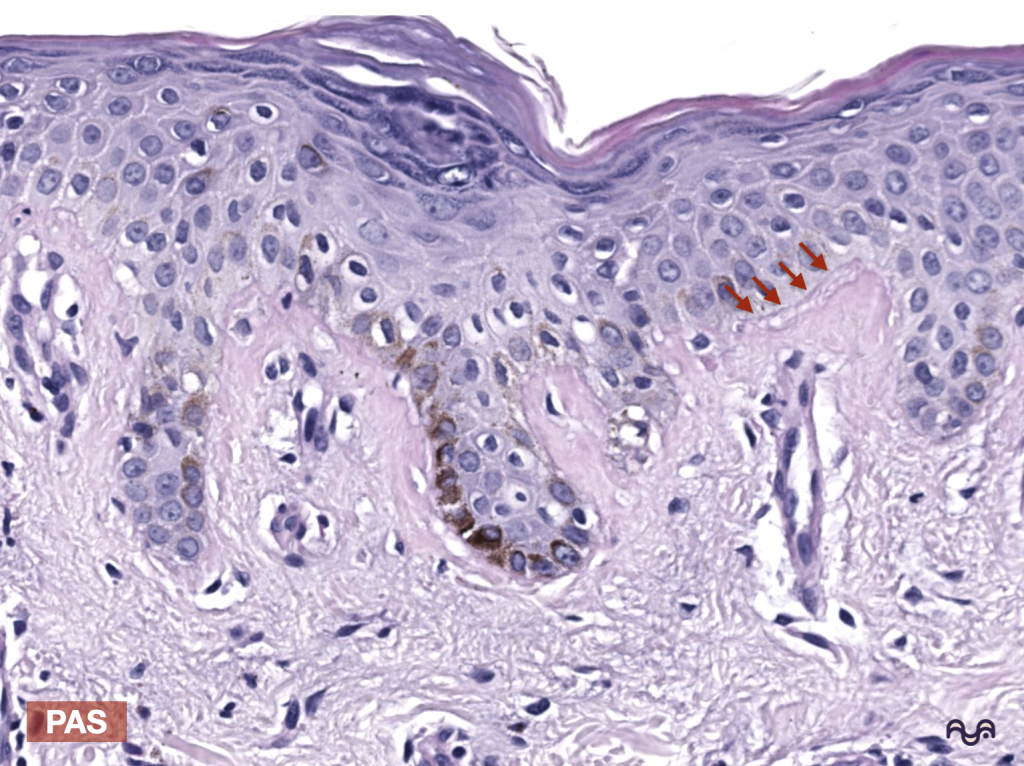

B) Tinción de PAS: cuándo y por qué ayuda

Cuándo: sospecha de interfaz sutil en H&E, necesidad docente de resaltar contorno, o evaluación comparativa entre zonas.

Por qué: la membrana basal contiene glucoproteínas/proteoglucanos que suelen teñirse con PAS, delineando una banda/contorno más evidente. Breitkreutz 2013

Si necesitas delinear MB: añade PAS (o revisa si el laboratorio tiene PAS disponible en set docente).

PAS: ayuda a delinear membrana basal por su composición rica en carbohidratos asociados. Breitkreutz 2013